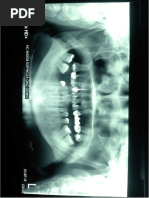

RADIOGRAFA PERIAPICAL #1

(Enanismo Radicular PIEZA 21)

ORIENTACIN DE LA PELCULA RADIOGRFICA

Repujado con la concavidad hacia adelante (vista hacia el paciente) y con

direccion hacia oclusal o incisal

Radiografa periapical perteneciente al cuadrante superior derecho e

izquierdo.

NOTACION DENTARIA

La radiografa corresponde al Cuadrante nmero 1 y 2, con visibilidad de

las piezas 11, 21, 22

INTERPRETACION PIEZA 21

La radiografa nos muestra

RAIZ

TERCIO APICAL

Estructura dentaria normal

El tamao radicular no concuerda con el tamao de la

corona por lo que es compatible con enanismo

radicular.